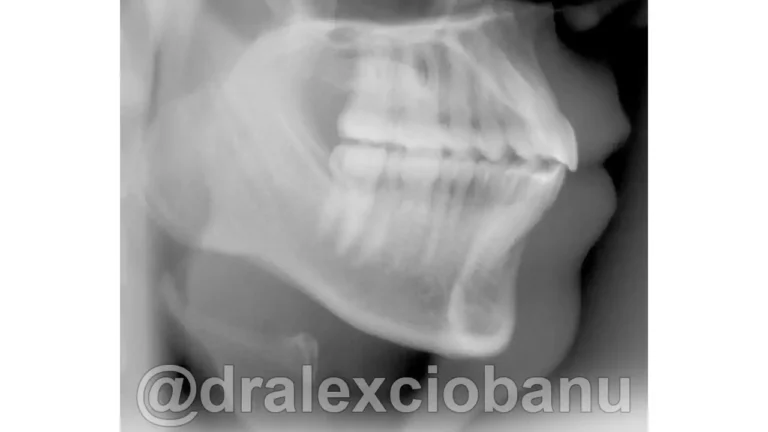

I brackets linguali possono allineare sia le corone che le radici dei denti, in modo che siano perfettamente posizionati l’uno accanto all’altro in posizione corretta. È spesso difficile ottenere questo posizionamento utilizzando gli allineatori rimovibili, specialmente quando si tratta di correggere le rotazioni dei canini. I brackets linguali fissi possono posizionare perfettamente i canini e i denti anteriori nella posizione corretta, come mostrato nella radiografia orto panoramica al termine della terapia.

Abbiamo corretto il morso ed ottenuto il perfetto allineamento dei denti.

Tempo totale di trattamento: 10 mesi.